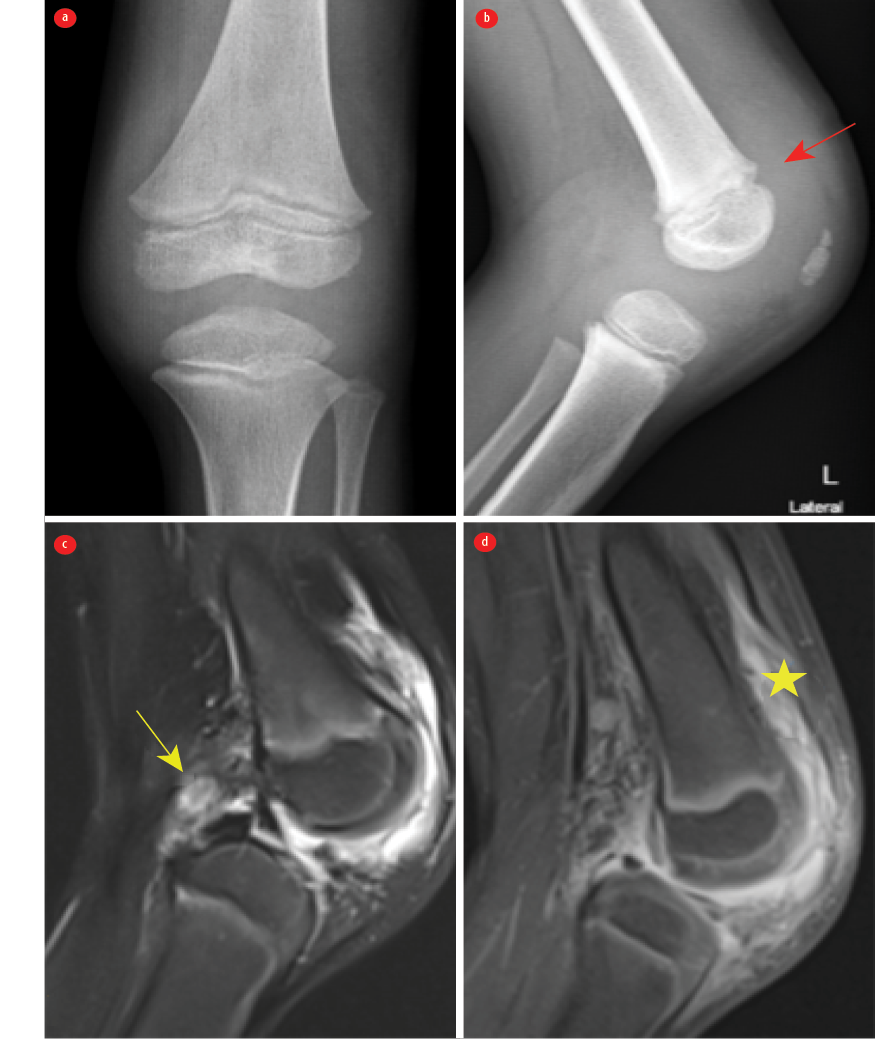

A five-year-old previously healthy male child presented to a tertiary center in Oman with a one-day history of high-grade fever reaching up to 39 oC, left knee pain, swelling, and restricted movements. There was no history of preceding infectious symptoms, trauma, animal exposure, or travel. His immunization was up-to-date. He was born at 33 weeks of gestation, and at two weeks of life, he was managed for culture-negative septic arthritis complicated by osteomyelitis of the proximal tibia. He underwent a left knee arthrotomy and was managed with six weeks of intravenous antibiotics. He made a full recovery. The physical examination revealed a temperature of 39 oC, associated with tachycardia of 149 beats/minute and tachypnea of 32 breaths/minute. His left leg was fixed and flexed, and his left knee was swollen, erythematous, hot, tender, and externally rotated with a healed scar from the previous surgery. The other systemic examinations were unremarkable. Initial investigations revealed leukocytosis (white blood cells) of 18.2 × 109/L (4.5 – 14.5 × 109/L) and a C-reactive protein of 309 mg/L (0–5 mg/L). Magnetic resonance imaging of the left knee showed a moderate left knee joint effusion with complex internal contents, septa, and thickened and enhanced synovium with extensive periarticular soft tissue edema [Figure 1]. Gram-positive cocci in chains grew from the joint fluid. Informed consent was obtained from the patient’s family.

Figure 1: Radiographs of the left knee (a) anteroposterior and (b) lateral views revealed periarticular soft tissue swelling, which is better seen on the lateral radiograph. We observed suprapatellar pouch effusion (red arrow). No fractures or destructive bony lesions were observed, and the joint space was preserved. (c) Sagittal T2 FS MRI of the knee showing enlarged lymph nodes in the popliteal fossa were also noted (yellow arrow). (d) Post-contrast T1 FS MRI of the knee revealed a small knee joint effusion with synovial thickening and periarticular soft tissue edema. There was thick enhancing synovium on the post-contrast images (star).

The enhancement suggests features of septic arthritis and synovitis, with no evidence osteomyelitis or a sizable collection [Figure 1]. He was started on intravenous cefazoline and underwent a left knee open arthrotomy. Streptococcus agalactiae, susceptible to ampicillin, grew from his synovial fluid. He was slow to improve after the first arthrotomy, but improved significantly after the second, which was done 12 days after the first procedure. He was managed with three weeks of antibiotics post the second washout. He had a full recovery at the two-month follow-up.